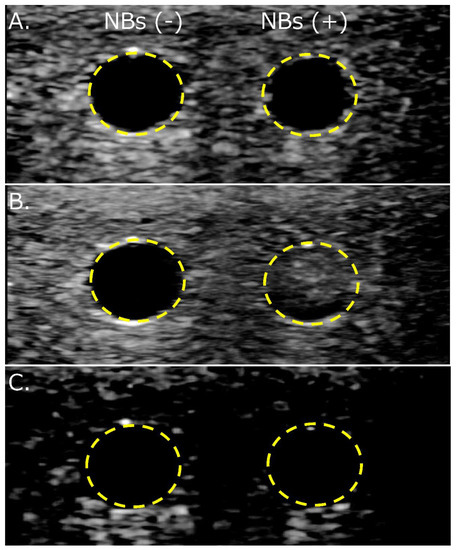

3.4. NBs Regenerated after Lyophilization Are Echogenic

3.5. NBs Regenerated from Lyophilized Materials Act as Cavitation Nuclei in mRNA Sonoporation